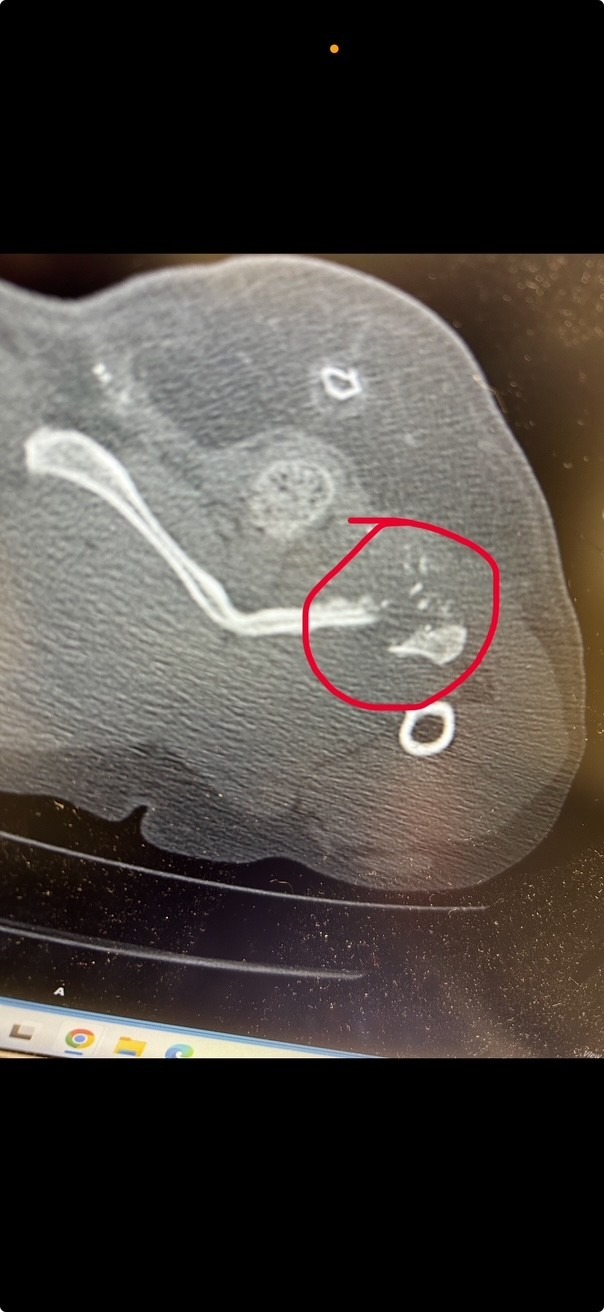

The results were devastating. Mae has bone fragments and pieces of the bullet inside her. The infection is spreading, and the vets told us that the only way she can survive is with surgery to remove the shattered bone and the bullet fragments. This surgery is estimated at $5,500.